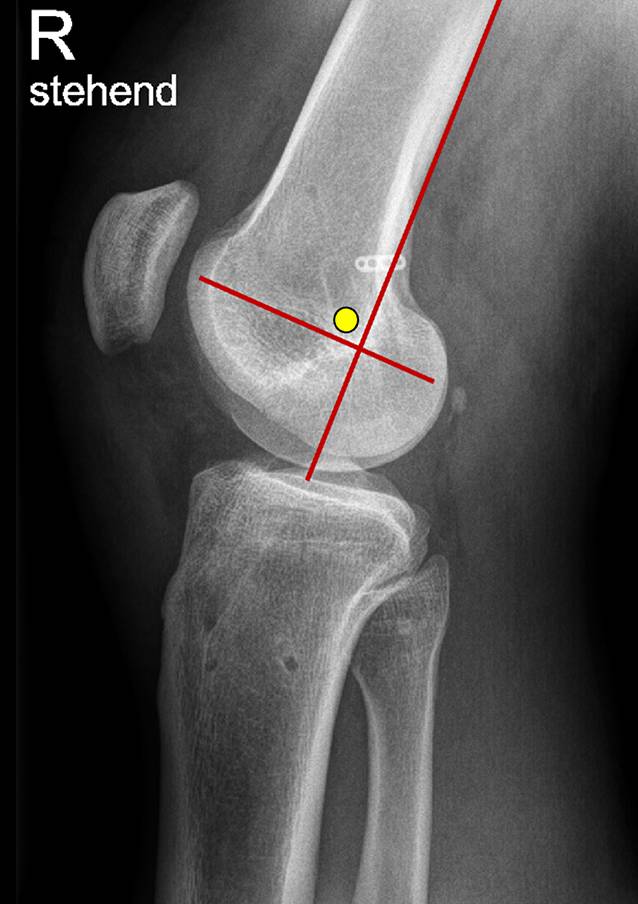

Abb. 2

Insertionen des oberflächlichen Seitenbands (sMCL) im streng seitlichen Röntgenbild der distalen Femurkondylen. Die Hilfslinien bestehen aus einer Tangente der dorsalen Femurkortikalis und einer rechtwinkligen Linie am Schnittpunkt der ersten Linie mit der Blumensaatlinie. Die gelbe Markierung zeigt den anatomischen Insertionsbereich des sMCL. Dieser liegt ventroproximal des Schnittpunkts der beiden Hilfslinien. (Nach [12])

Eine große Hilfe bei der Rekonstruktion der einzelnen Bandanteile des Innenbandkomplexes stellt die Kenntnis über die radiologisch-kontrollierten topographischen Lagebeziehungen der Insertionsbereiche der MCL-Anteile dar. Hier wurde durch Athwal et al. insbesondere die femorale Platzierung des sMCL und dMCL im streng seitlichen Röntgenbild im Vergleich zu vorherigen Darstellungen korrigiert ([3]; Abb. 2).